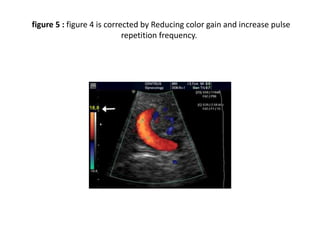

figure 4 : Aliasing of color doppler imaging and artefacts of color. Color

image shows regions of aliased flow (yellow arrows).

figure 5 : figure 4 is corrected by Reducing color gain and increase pulse

repetition frequency.

figure 4 :Aliasing of color doppler imaging and artefacts of color. Color image shows regions of aliased flow (yellow arrows).

figure 5 :figure 4 is corrected by Reducing color gain and increase pulse repetition frequency.